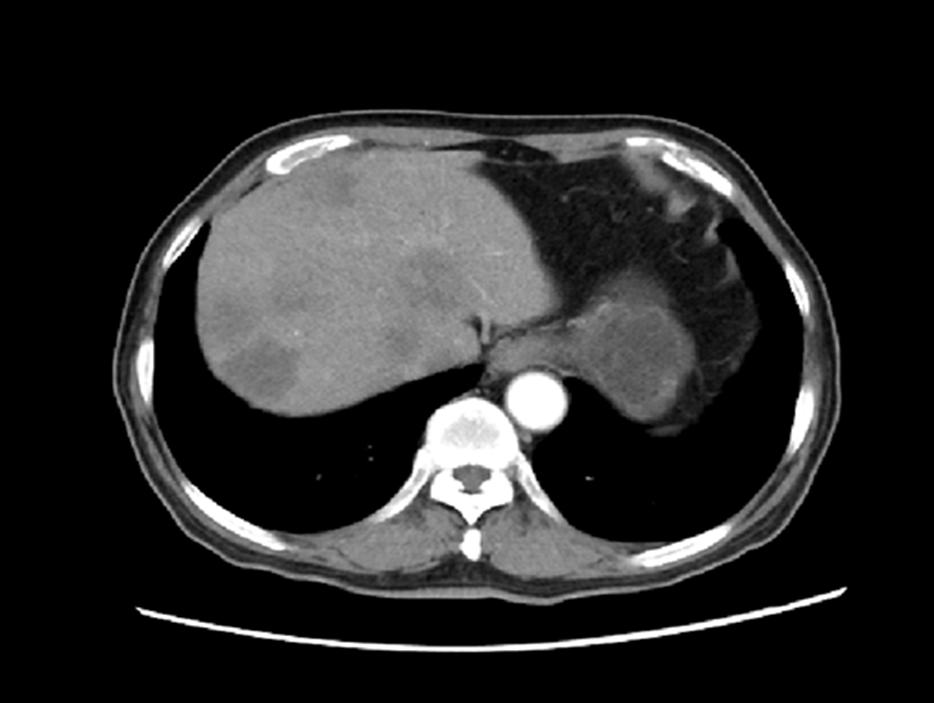

2020.1.5影像学评价:腹部CT:肝脏多发结节,较前增多增大,考虑进展(图3)。

图3. 腹部CT(上:2019.11.18,下:2020.1.5)